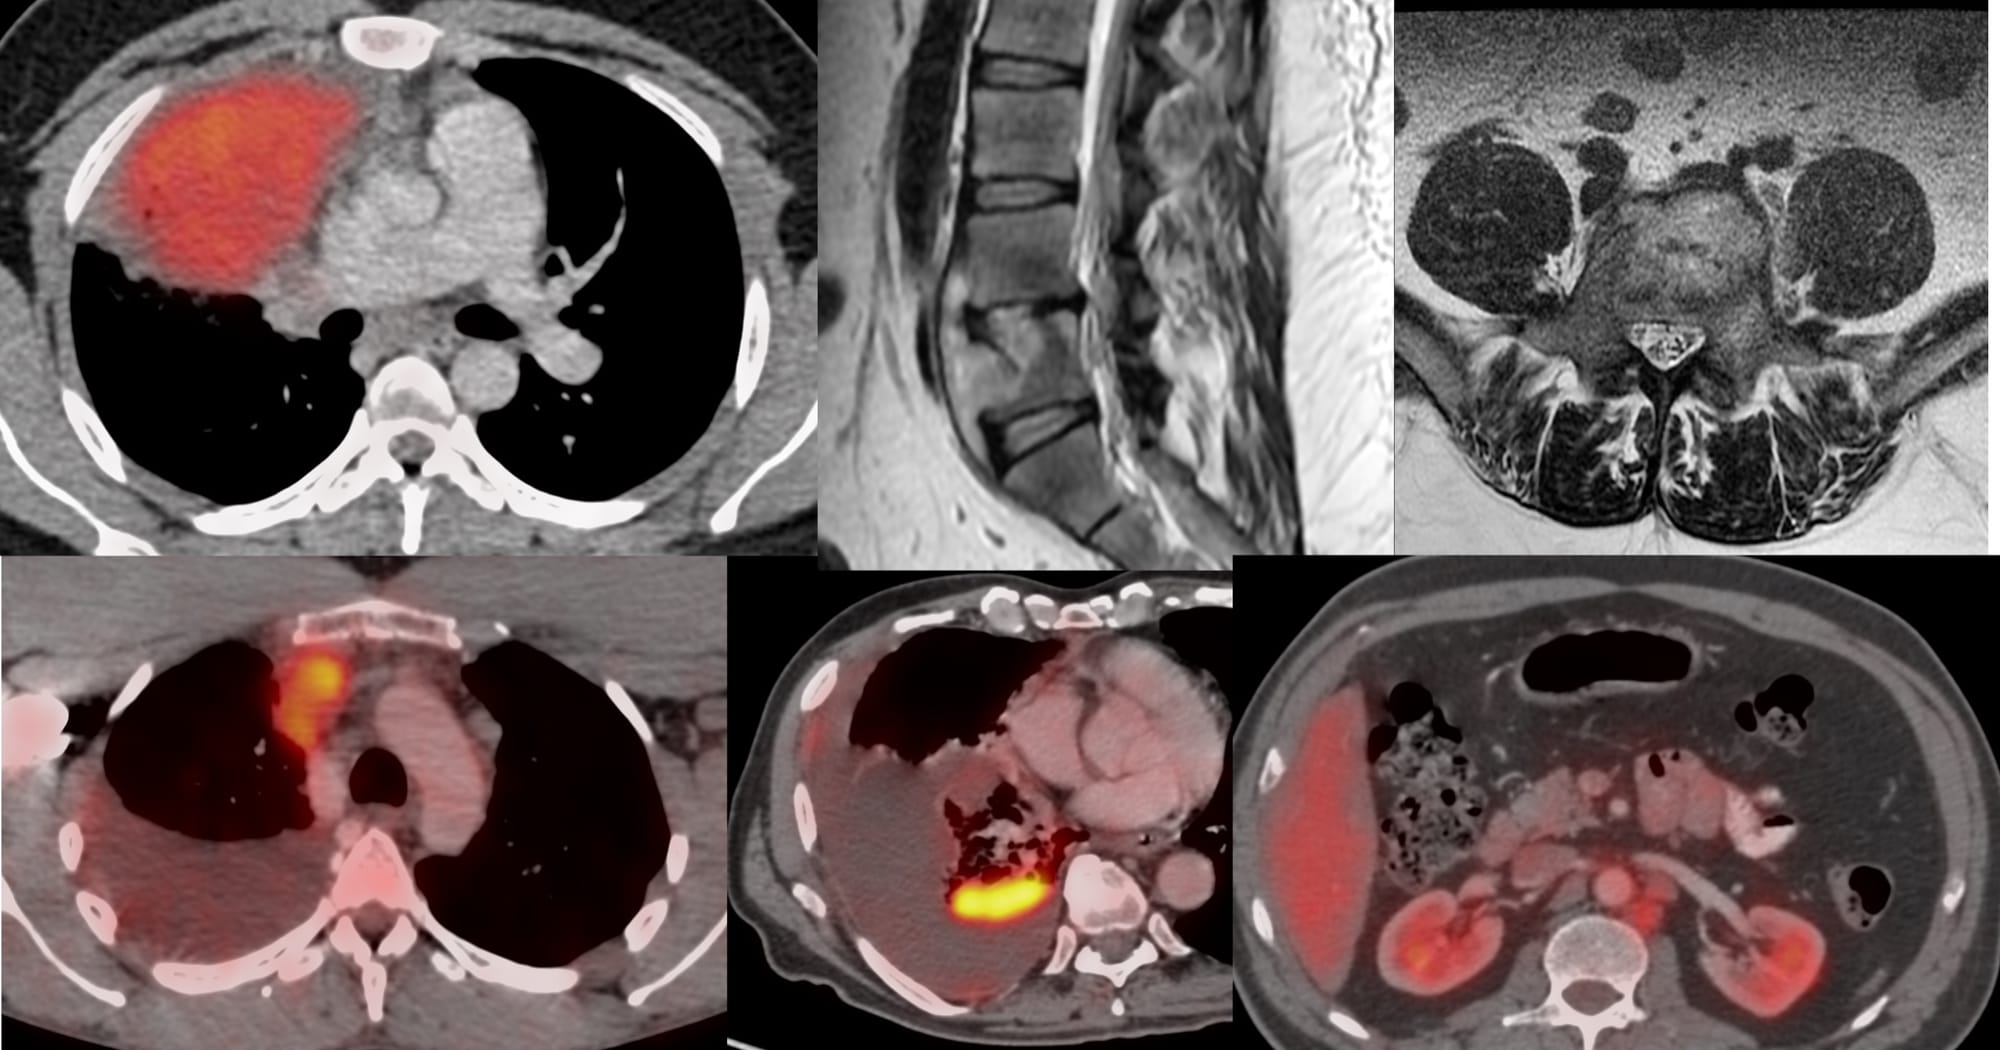

Case of the Day 100 - 2025 09 10 - T2 Dark Thoracic Spinal Vertebral Lesion - Transpedicular Biopsy

Bhavin Jankharia - 14 September 2025